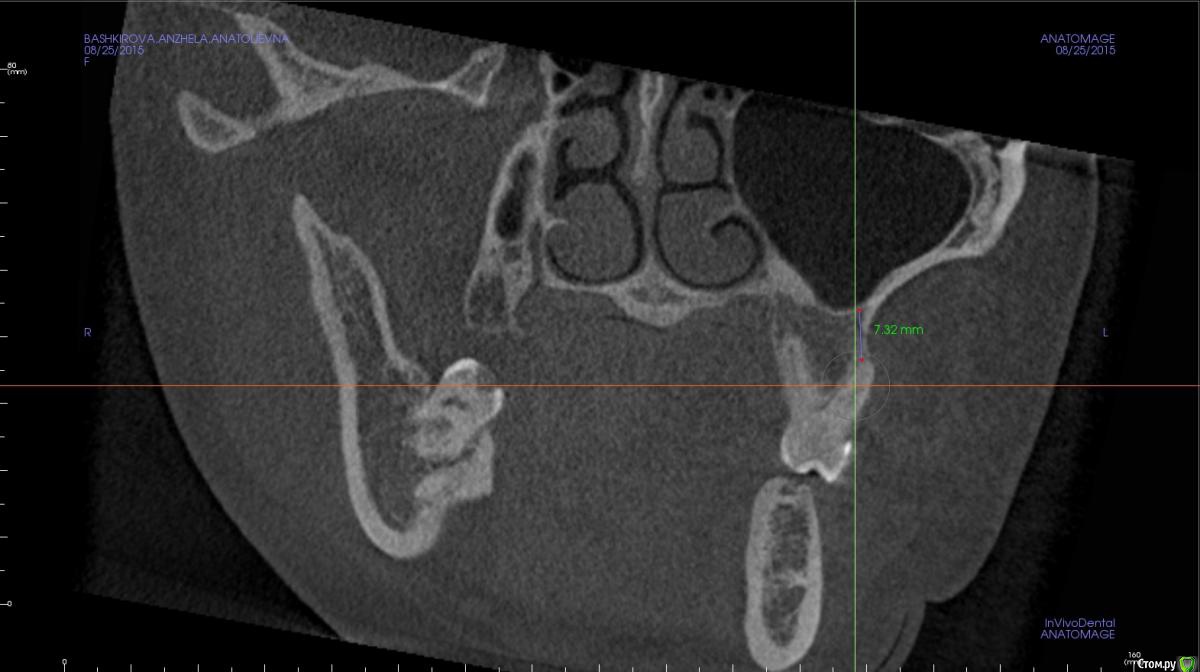

Rustam161 Опубликовано 26 августа, 2015 Поделиться Опубликовано 26 августа, 2015 Здравствуйте доктора.Необходимо произвести интрузию 26 и 27 зубов,но при осморте расположения щечных корней 26 зуба обнаружил их вестибулярное положение на снимке.В таком случае можно проводить интрузию или необходимо находить какое-то иное решение ?? Ссылка на комментарий

azerty Опубликовано 19 января, 2017 Поделиться Опубликовано 19 января, 2017 Что бы не плодить темы, подскажите коллеги,возможна ли интрузия моляров на верхней челюсти при очень близком расположении корней рядом с гайморовой пазухой?Не произойдет ли перфорация дна пазухи?Снимки прикреплю завтра,спасибо! Ссылка на комментарий

Opdihatop Опубликовано 22 января, 2017 Поделиться Опубликовано 22 января, 2017 Перфорации не будет скорее всего (особенно, если силы давать небольшие), но и интрузия идти будет очень медленно. Ссылка на комментарий

orthophil Опубликовано 6 февраля, 2017 Поделиться Опубликовано 6 февраля, 2017 Господа! О какой перфорации вообще идет речь. Моляры же не молотком вколачивать придется. А вот расстояние между верхушками и гайморовой пазухой уменьшится. Ссылка на комментарий